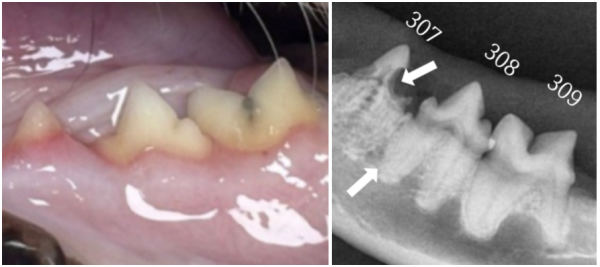

dda74ec2cbe3c1a8b77df26586ebe9fb_1765777862_6527.png

치료 후 관리와 보호자 안내

치료가 완료된 후에도 잔여 치아의 스케일링 및 발치 부위에 대해

자세한 상담을 받으실 수 있으며

대부분의 보호자님들이 집에 돌아가시면

정확하게 발치한 치아에 대한 정보를 잊어버리시는 경우가 많아 5일 이내

치과 리포트를 작성해 보내드리고 있습니다.

(발치 후 방사선 사진 포함)

이를 통해 치료 전 후 상태를

명확히 확인하실 수 있습니다.

dda74ec2cbe3c1a8b77df26586ebe9fb_1765777874_622.png